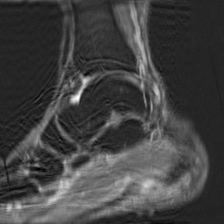

Object Movement

MRI OmniMedVQA Disease Diagnosis

Object Movement - L0 (Original)

L0

L0 (Original)

Question

What is the visual finding in this image?

A Rotator cuff tear B Plantar fascia pathology C Bunion D Golfer's elbow

Ground Truth: B. Plantar fascia pathology